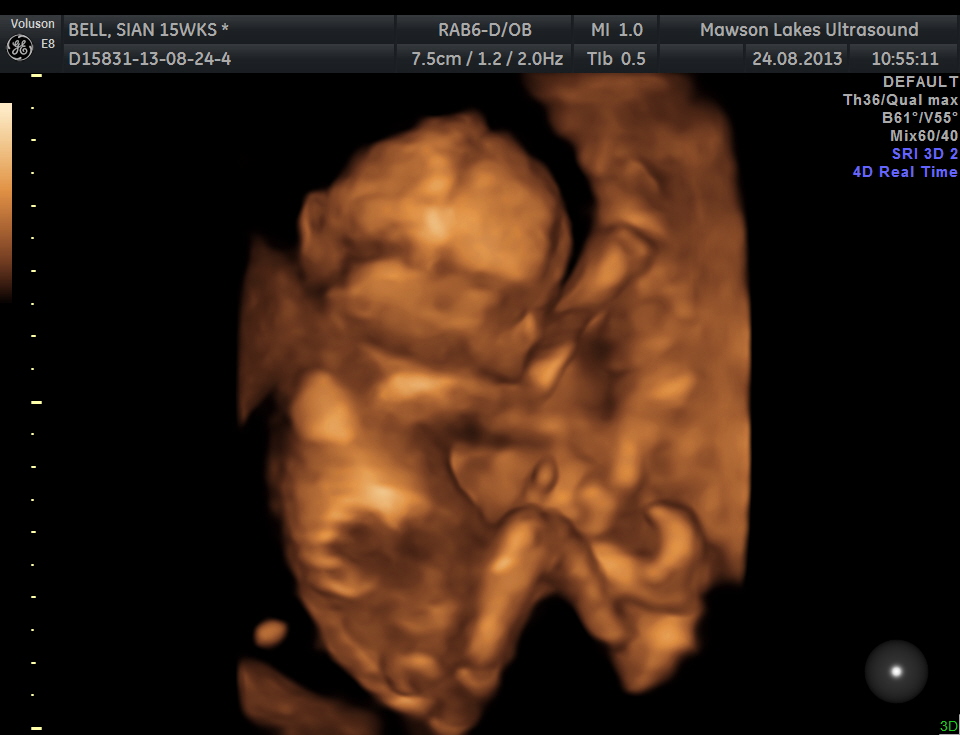

UPDATE: I just came back to let you guys know I had my 3d/4d gender scan today (15w4d) and baby is a GIRL!! so so happy!!!

Attachment 13387